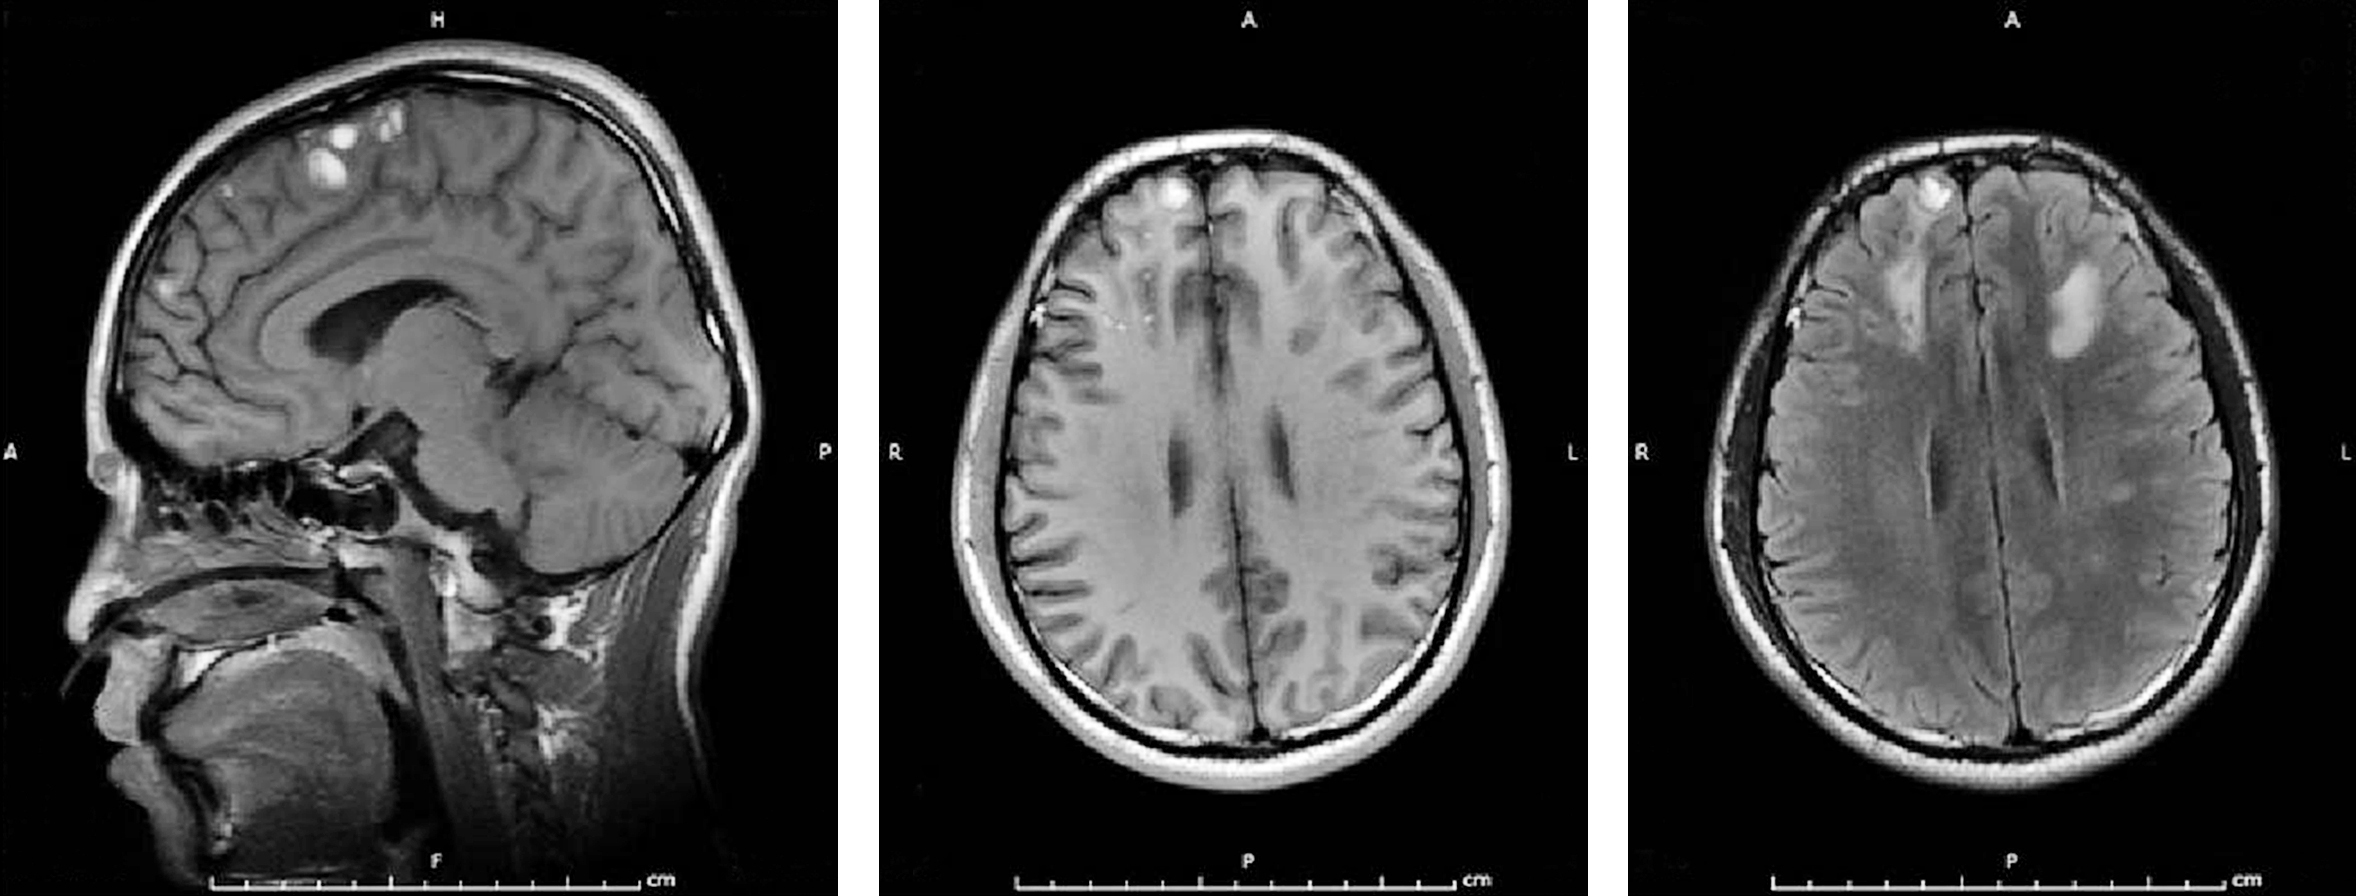

MR表现:若病变无出血,T2WI表现为脑白质、灰白质交界处和胼胝体、脑干及小脑散在、分布不对称的点片状异常高信号,T1WI呈等或低信号。若有出血灶,急性期病灶呈T2WI低信号,T1WI等或高信号,周围可见水肿信号;亚急性和慢性期出血的信号强度随时间而异。DWI对诊断超急性期及急性期脑弥漫性轴索损伤具有很高的敏感性,显示出血为低信号而水肿为高信号;SWI则对微小出血有更高的检出能力(图2-4-7)。

图2-4-7 弥漫性轴索损伤MR影像表现

单发或是多发的长T1WI,长T2WI信号

MR检查:比CT检查更为敏感。弥漫性轴索损伤如为非出血性,典型表现为T2WI可见脑白质、脑灰白质交界处和胼胝体、脑干及小脑散在、分布不对称的点片状异常高信号,T1WI上述病灶呈低或等信号。急性期出血病灶在T2WI呈低信号,T1WI呈等信号,周围可见高信号水肿。亚急性期和慢性期出血表现为高信号。损伤后期由于脑白质损伤、轴突变性、萎缩,可使相应部位的脑室扩大。

对弥漫性轴索损伤的诊断价值而言,MRI比CT检查具有更高的敏感性,且T2WI优于T1WI。